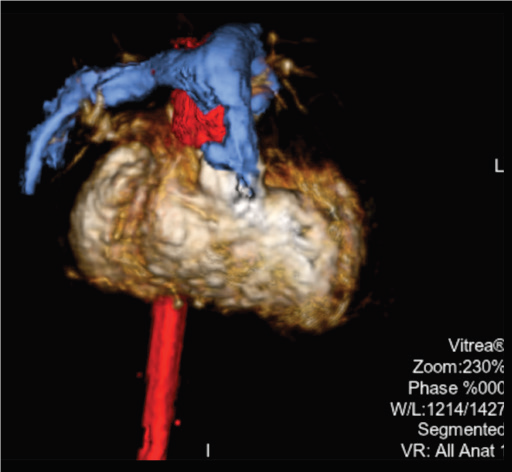

Multi-modality fusion*

Технологія 3D накладання об’єму 3D на «живе» флюороскопічне зображення. Можливе накладання як отриманого на ангіографі 3D об’єму, так і об’єму КТ/МРТ.

Програмне забезпечення MM Roadmap (або Multi-modality fusion) забезпечує додаткову інформацію завдяки 3D-візуалізації судинної анатомії, що успішно використовується при плануванні та навігації транскатетерної заміни клапану для лікування вроджених вад серця.

MM Roadmap дозволяє суміщувати 2D-флюороскопічні зображення з раніше отриманим 3D-об’ємом. Це може бути КТ або МРТ об’єм при чому незалежно від виробника сканера, або з ангіографічної системи Canon.

Суміщене зображення на моніторі змінюватиметься синхронно в залежності від нахилу С-арки, зміни SID, поля огляду, висоти та положення деки столу.

Можливість використання програмного забезпечення MM Roadmap під час складних втручань допомогає скоротити тривалість опромінення та об’єм введеної контрастної речовини..